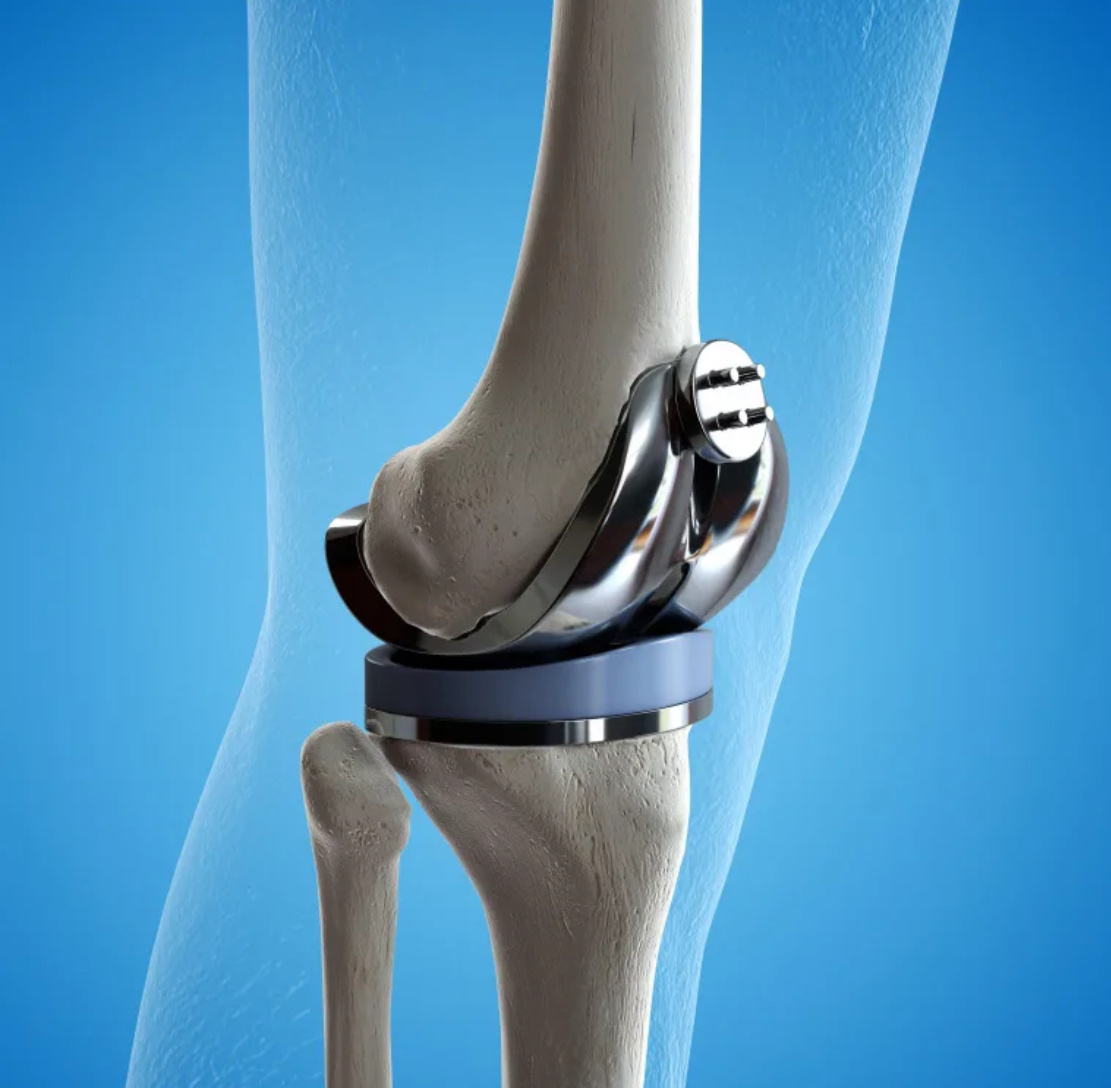

Кто плотно занимается эндопротезированием, тот регулярно слышит от пациента вопрос о «самом лучшем эндопротезе». Кто-то для себя хочет, кто-то родителям. Посыл понятен: если уж делать операцию, то уж с самым качественным/надёжным/лучшим суставом. Полностью согласен с этим подходом, сам рассуждал бы так же. Но: есть одно большое НО. Даже если не вдаваться в детали конструкций искусственных суставов, производителей и т.д. Если допустить, что все протезы супер. Идеальны. Вечны. Что может пойти не так? Как ни странно, многое. Я бы разделил эту тему на две части: понятное и непонятное. К понятному можно отнести дефекты операции (неправильно установлен сустав, инфекция, не те размеры и т.д.). К непонятному - когда все хорошо и правильно, а проблема есть. Сегодня расскажу о непонятном (про понятное неоднократно писал раньше) на примере двух свежих случаев. СЛУЧАЙ ПЕРВЫЙ Женщина хорошо за 60. В Германии 10 лет назад сделала одномыщелковое протезирование коленных суставов (писал о таком недав

Женщина хорошо за 60. В Германии 10 лет назад сделала одномыщелковое протезирование коленных суставов (писал о таком недавно). Через год из-за расшатывания одного протеза заменили его на тотальный. Еще через пару лет и второй заменили на тотальный. В обоих случаях инфекции не было - асептическое расшатывание. Сразу после последней операции в колене нестабильность, ощущение неустойчивости. Как-то приспособилась, ходила, ограничивала себя, но терпела. Наконец, терпение кончилось. Пошла у нас по врачам, и тут мнения разделились. Одни считали, что есть нестабильность сустава (то есть, связки не работают), другие - что проблема в нестабильности самого эндопротеза.

Вопросов - масса. Сам протез отличный, американский, в целом установлен хорошо. Но - нужна была немного другая конструкция, полиэтиленовый вкладыш должен был быть толще, и - вишенка на торте - весь костный цемент, которым протез приклеивается к костям, остался при удалении протеза на протезе!